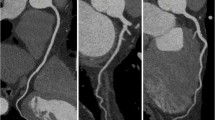

Many subsequent analyses have confirmed that BMS results in LLL of 0.7–1.0 mm. DES revolutionized interventional cardiology because of their ability to reduce neointimal proliferation and restenosis. In a meta-analysis of 29 trials comparing various DES with nearly 9,000 patients undergoing follow-up, protocol-mandated angiography, LLL proved to be an excellent indicator of BAR (R 2 = 0.5301; P < 0.0001) and target vessel revascularization (TVR−R 2 = 0.4604; P < 0.0001) [23]. These data extended across five major platforms of DES (Figs. 3.1 and 3.2) and showed LLL of 0.13–0.56 mm. DES containing sirolimus or its analogues had TVR as low as 2.8 % (Table 3.1). Importantly, there was no threshold in this relationship, meaning that the lower LLL was, the lower the probability for revascularization was as well. Nearly 75 % of patients with angiographic restenosis needed TVR.

Relationship between in-stent loss (ISL) and binary angiographic restenosis (Adapted from Brener SJ, Prasad AJ, Khan Z, Sacchi TJ. The relationship between late lumen loss and restenosis among various drug-eluting stents: a systematic review and meta-regression analysis of randomized clinical trials. Atherosclerosis. 2011; 214(1):158–62. With permission from Elsevier)

Relationship between in-stent loss (ISL) and target vessel revascularization (TVR) (Adapted from Brener SJ, Prasad AJ, Khan Z, Sacchi TJ. The relationship between late lumen loss and restenosis among various drug-eluting stents: a systematic review and meta-regression analysis of randomized clinical trials. Atherosclerosis. 2011;214(1):158–62. With permission from Elsevier)